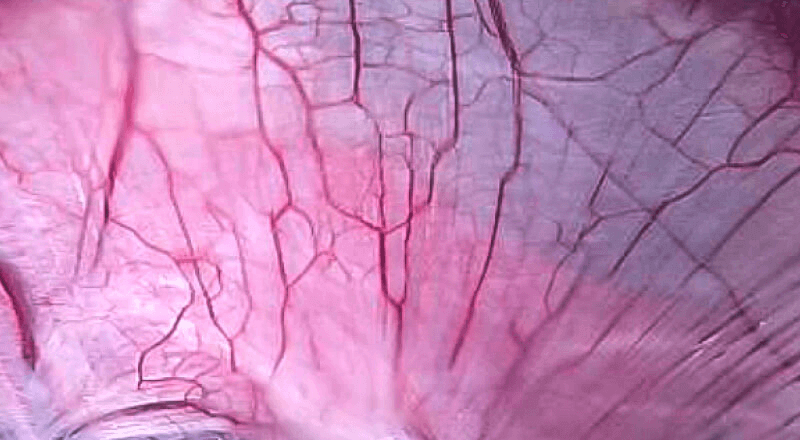

是一种基于血红蛋白对不同波长光吸收系数不同的原理而设计的智能染色成像系统,兼有电子染色和光学染色功能,能够凸显粘膜血管结构,有助于病灶部位识别和诊断,为临床医生术中判断提供参考信息。

血管对比度分布光谱曲线

VIST光谱

光电复合染色成像